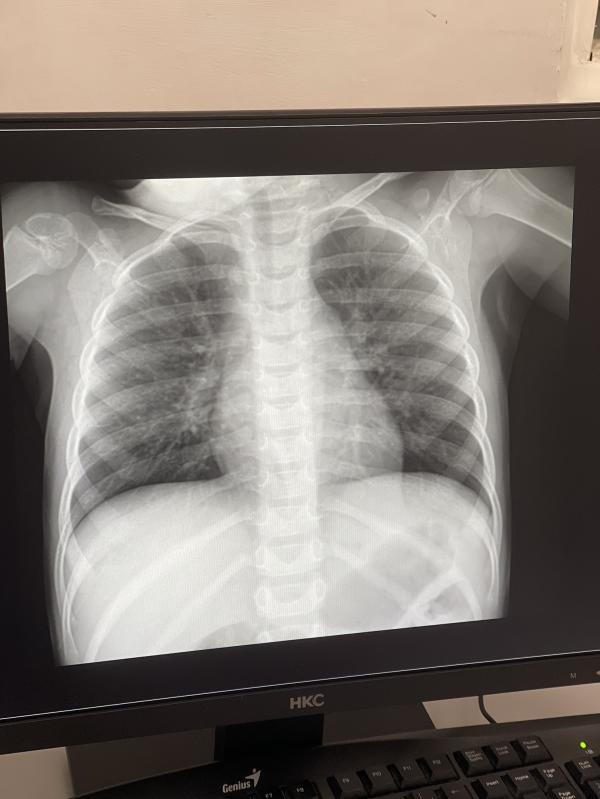

post image

Есть тут что-нибудь?

Бронхит скорее всего. Дала маршал дойл 🌿

А так, такие светлые рисунки были у нас и при бронхите, и при пневмонии.